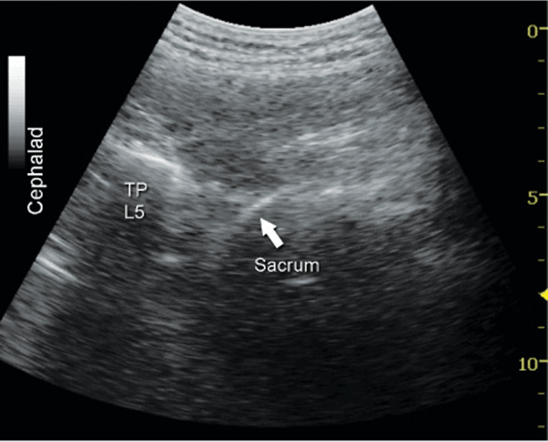

More recently, Karmakar and colleagues described the “trident sign technique,” which uses an easily recognizable ultrasonographic landmark, transverse processes, and an out-of-plane needle insertion. The trident sign technique derives its name from the characteristic ultrasonographic appearance of the transverse processes (trident) to estimate the depth and location of the lumbar plexus. After application of ultrasound gel to the skin over the lumbar paravertebral region, the ultrasound transducer is positioned approximately 3 to 4 cm lateral and parallel to the lumbar spine to produce a longitudinal scan of the lumbar paravertebral region (Figure 46-7). Then the transducer is moved caudally, while still maintaining the same orientation, until the sacrum and the L5 transverse process become visible (Figure 46-8). The lumbar transverse processes are identified by their hyperechoic reflections and acoustic shadowing beneath which is typical of bone. Once the L5 transverse process is visible, the transducer is moved cephalad gradually, to identify the L3-L4 level. The goal of the technique is to guide the needle through the acoustic window between the transverse processes (between the “teeth of the trident”) of L3-L4 or L2-L3 into the posterior part of the psoas major muscle containing the roots of the lumbar plexus (Figure 46-2B). After obtaining ipsilateral quadriceps muscle contractions, the block is carried out using the previously described injection and pharmacology considerations (Figures 46-9 and 46-10).

FIGURE 46-8. Transverse image of lumbar paravertebral space demonstrating sacrum and transverse process (TP) of L5. Starting the scanning process from the sacral area and progressing cephalad allows the identity of the individual transverse processes (levels). As the transducer is moved cephalad and the surface of the sacrum disappears, the next osseous structure that appears is the transverse process (TP) of L5.